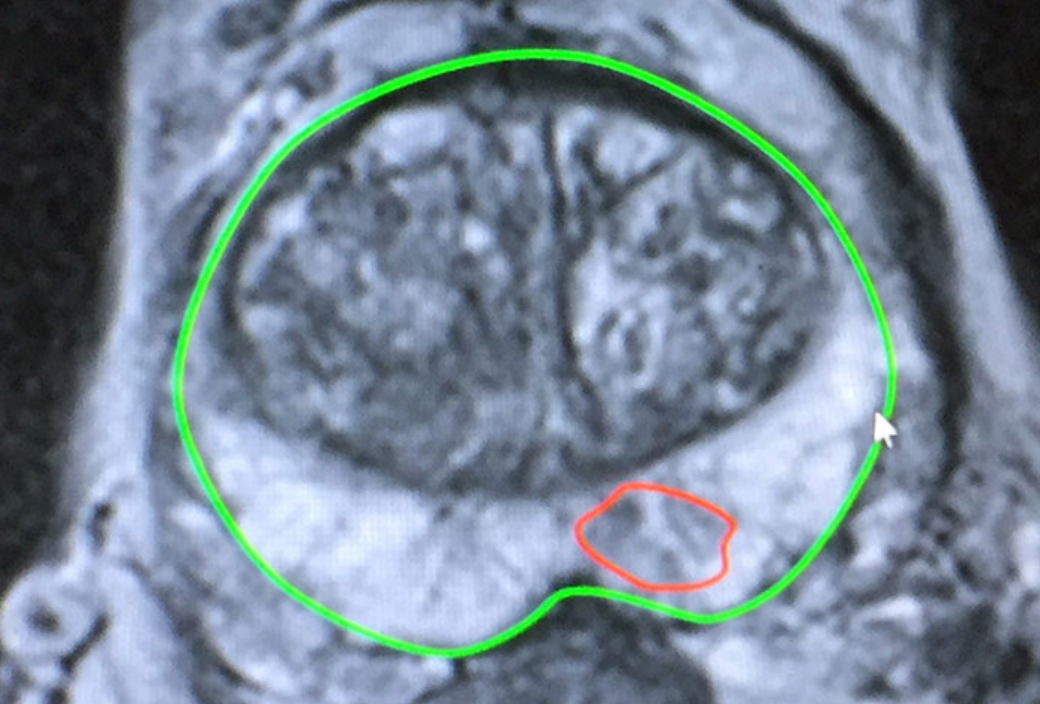

Led by Mr. Antoine Kass, A consultant Urologist in York, who performed thousands free hand TP biopsies, this course offers hands-on training in advanced transperineal prostate biopsy techniques.

Hands-on sessions with expert guidance, blending theory and practical experience seamlessly.